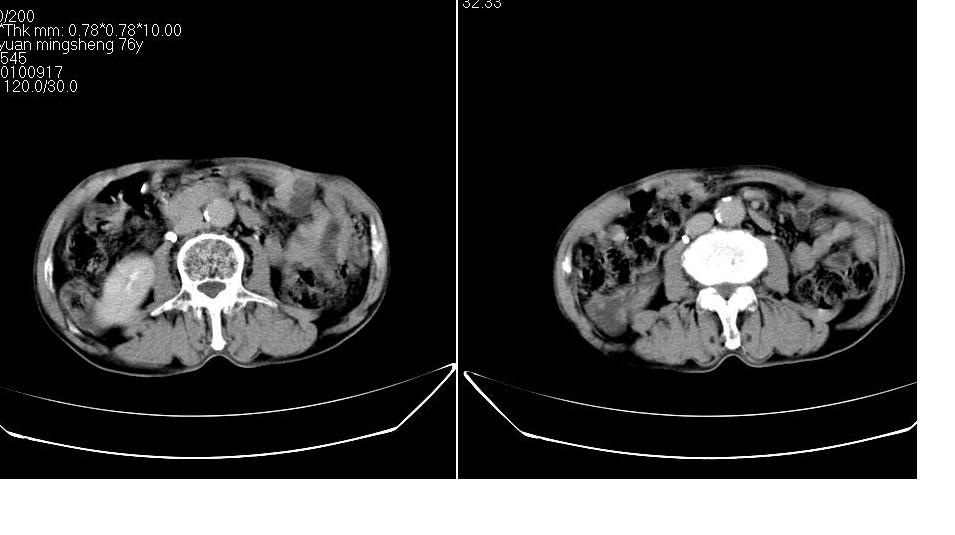

男,76岁,上腹部疼二天来就诊,彩超提示肝左叶占位,随后做上腹部ct平扫,今天做上腹部ct增强扫描,手工推药,效果不好,请谅解。

肝左叶s4肿块强化形式大概是:慢进慢出,逐渐强化----考虑血管瘤/腺瘤?{动脉期应更提前扫}。

1)肝右叶前段低密度灶,不排除肝癌可能;建议查afp。2)右肾上极囊肿。

肝内胆管积气扩张,胆囊增大,肝右前叶低密度灶,逐渐强化,一元论,胆系感染,局限性肝脓肿;右肾囊肿。

考虑肝s4段肝脓肿可能?未排除肝癌。右肾上极囊肿。